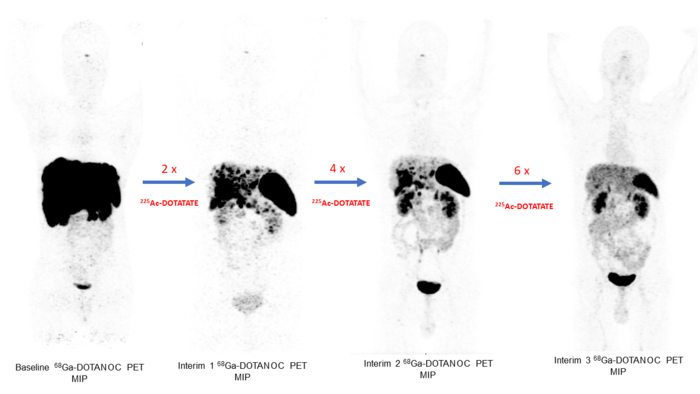

Vancouver, British Columbia, Canada —A targeted radionuclide alpha therapy, 225 Ac-DOTATATE, has been shown to have long-term anti-tumor effects in patients with advanced-stage gastroenteropancreatic neuroendocrine tumors (GEP-NETs). Results from the Phase II study showed promising survival rates, high response rates and an acceptable toxicity profile, making 225 Ac-DOTATATE a potential treatment option for patients who have exhausted other forms of therapy. This research was presented at the Society of Nuclear Medicine and Molecular Imaging 2022 Annual Meeting and was selected as the meeting’s Abstract of the Year.

In the study, researchers aimed to evaluate the long-term efficacy, survival outcomes, and safety of the targeted radionuclide alpha therapy 225 Ac-DOTATATE in GEP-NET patients. Eighty-three GEP-NET patients (including 56 patients with prior 177 Lu-DOTATATE treatment and 27 177 Lu-DOTATATE-naïve patients) received systemic treatment with 225 Ac-DOTATATE intravenously at eight weekly intervals.

Hematologic, kidney and liver function tests were performed before and after each cycle. Tumors were measured using RECIST 1.1 criteria at baseline and after two cycle intervals. Overall survival, radiographic progression-free survival, objective tumor response, and treatment-related adverse events were assessed.

After the treatment course, two patients (2.7 percent) had complete response, 32 (43.2 percent) had a partial response, 25 (34 percent) had stable disease, and 15 (20 percent) had progressive disease. Minimal toxicities were noted after treatment with 225 Ac-DOTATATE.